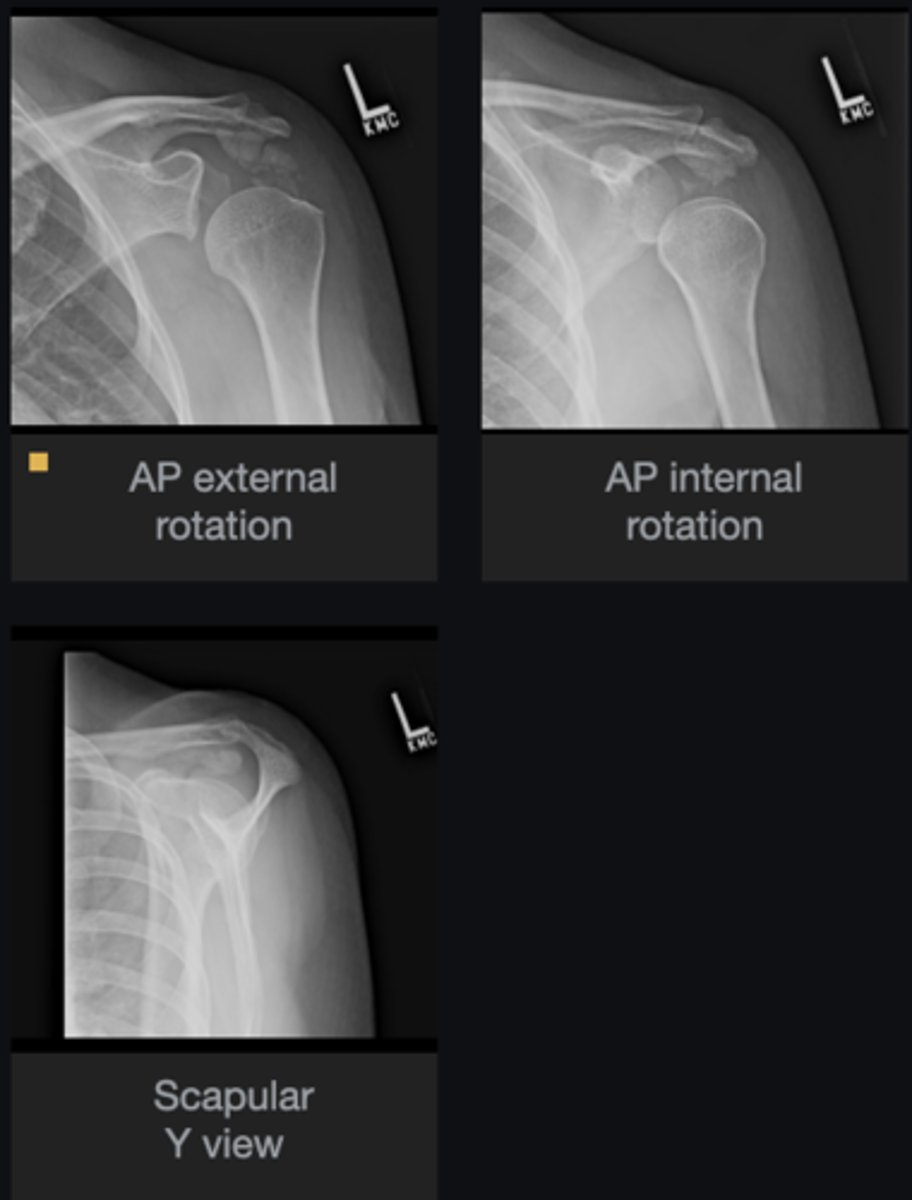

- Increased acriohumeral interval

- Glenohumeral subluxation

- Globular calcification in acromiohumeral interval

List the abnormal findings

Hydroxyapatite deposition disease

Diagnosis?

- Continue chiropractic care as long as patient is improving

- If patient not improving, orthopedic referral

Next step?